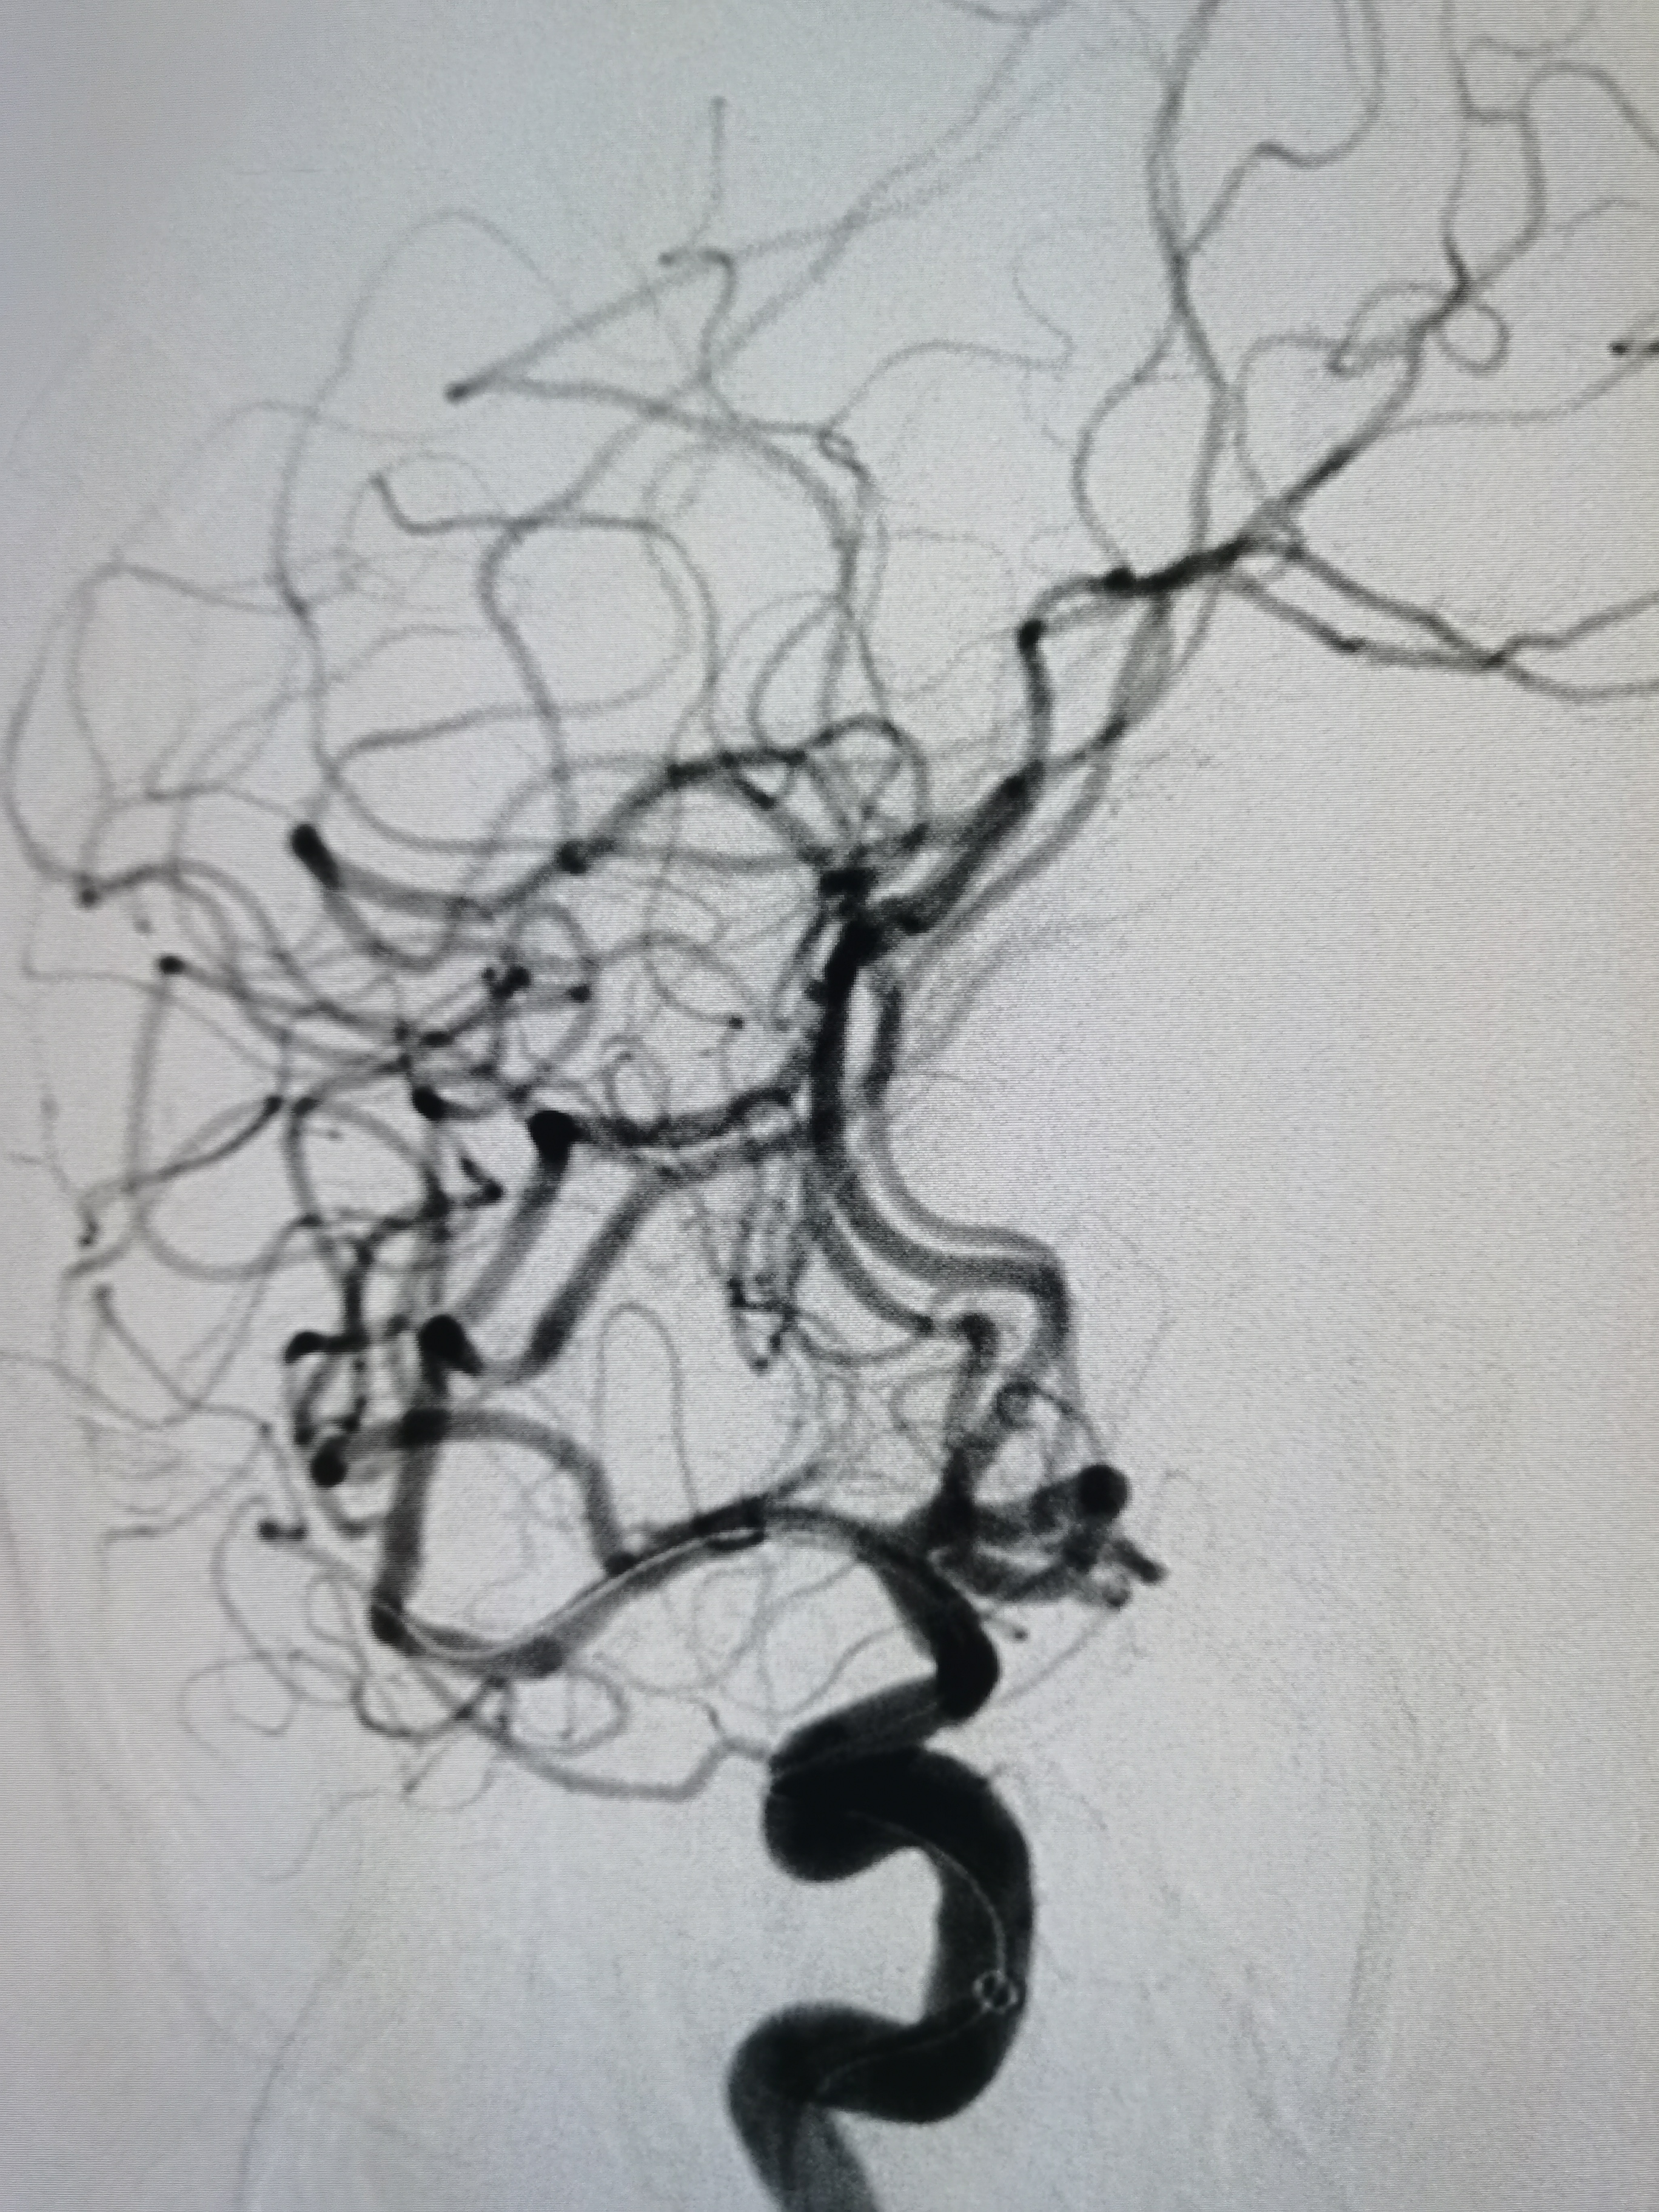

颅内侧位显影可。

右侧大脑中动脉M1段重度狭窄。

右侧大脑中动脉M1段重度狭窄,病变处存在豆纹动脉。

患者右侧大脑中动脉M1段重度狭窄,病变处存在豆纹动脉分支,具备介入治疗指征,手术风险在于血管夹层,破裂及穿支闭塞可能,向患者家属详细交代病情及风险后,家属积极要求介入治疗。拟行右侧大脑中动脉球囊扩张备支架成形术。